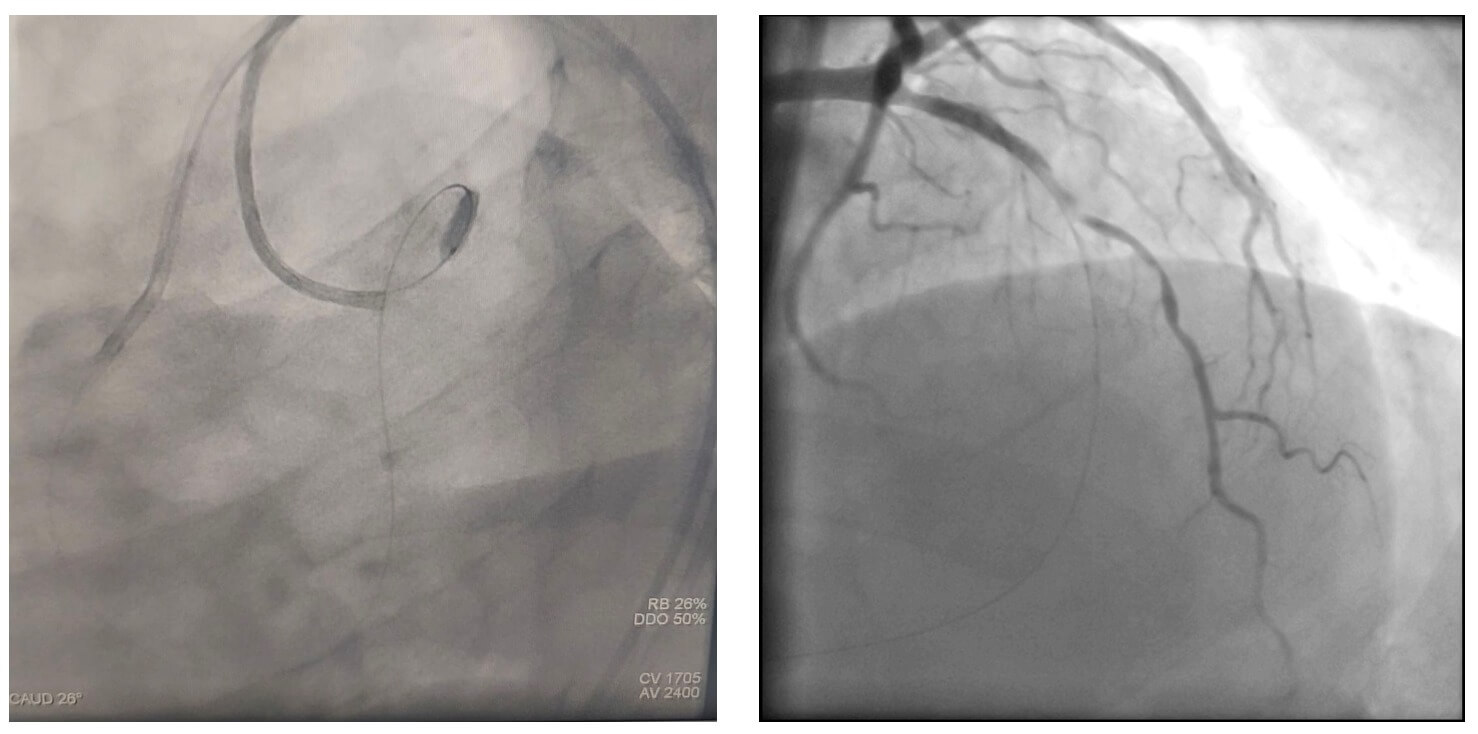

Se avanzó una guía intracoronaria Asahi Sion Black desde la arteria coronaria derecha, siguiendo el trayecto de una de las ramas septales, logrando acceso al tercio medio de la arteria descendente anterior izquierda, con soporte de microcatéter Turnpike. Posteriormente, la guía fue reemplazada por una de 300 cm para su externalización a través del catéter ubicado en el tronco de la coronaria izquierda.

Durante la externalización, el paciente presentó inestabilidad hemodinámica, evidenciándose una disección coronaria en la arteria coronaria derecha. Se procedió a la implantación de un stent, con mejoría clínica inmediata, lo que permitió continuar con el procedimiento planificado.

Posteriormente, se logró la predilatación de la oclusión con balones de bajo perfil y se implantó un stent DEStiny en el sitio de la lesión. Tras la apertura de la arteria, se identificó una lesión en la zona de reentrada (sitio de aterrizaje de la guía retrógrada desde la arteria coronaria derecha), por lo que se avanzó una guía por vía anterógrada y se implantó un segundo stent.